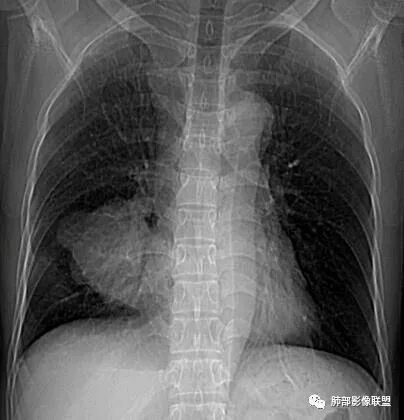

【每日晨读】一例“肺肉瘤”的套路分析

南边:男性,50岁

征象分析

南边:深分叶、大肿块

南边:主体在下叶前基底段

南边:边缘膨隆

南边:中叶、下叶背段支气管推移

南边:中叶支气管腔内似有粘液栓,外侧段有炎性病变

南边:结果:肉瘤